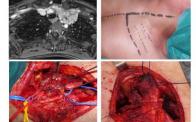

Thoracic surgical oncology

Chest wall resection and reconstruction

Thoracic outlet syndrome